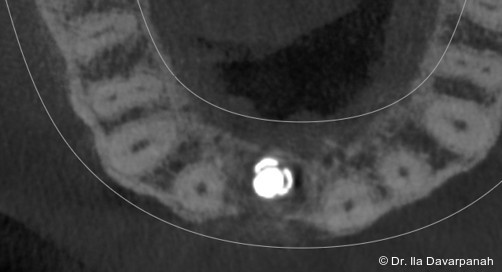

Postoperativ kam es trotz korrekter Implantatpositionierung und regelrechter Sofortversorgung zu einer Fraktur des Implantatkörpers im Bereich der Implantatschulter. Die radiologische Diagnostik mittels Röntgen und DVT zeigte ein Aufplatzen des Implantats im Übergangsbereich zwischen Konusverbindung und Implantatplattform. Das Frakturmuster deutete auf eine strukturelle Überlastung im hoch beanspruchten Schulterbereich hin. Implantatfrakturen stellen insgesamt eine seltene, jedoch für Patient und Behandler belastende Komplikation dar. Sie treten bevorzugt in Regionen mit erhöhten Biege- und Querkräften auf, insbesondere in der Frontzahnregion und bei frühzeitiger funktioneller Belastung.

Zur Erreichung einer hohen Primärstabilität wurde ein Implantat mit aggressivem Gewinde bei einem Außendurchmesser von 3,5 mm und einem Kerndurchmesser von ca. 2,8 mm eingesetzt. Ergänzend erfolgte eine unterpräparierte Bohrung. Solche Kombinationen aus Gewindedesign, Implantatgeometrie und Bohrprotokoll sind in der klinischen Praxis etabliert, erfordern jedoch eine sorgfältige Risikoabschätzung hinsichtlich der mechanischen Belastung des Implantatkörpers.